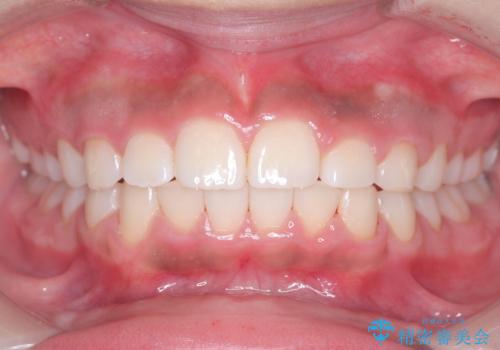

- 患者様は前歯の突出を主訴に来院されました。診査の結果、上顎の前歯が前方に傾斜しており、口元がやや突出して見える状態でした。一般的にこのようなケースでは抜歯矯正が選択肢となりますが、**患者様が抜歯を希望されなかったため、非抜歯での遠心移動(奥へ動かす治療)を計画しました。そのため、リンガルアーチ(歯の裏側に装着する装置)とTAD(歯科矯正用アンカースクリュー)**を併用し、上顎の歯を後方へ移動させながら噛み合わせを整える方法を選択しました。

まず、上顎にリンガルアーチを装着し、歯列の幅を適正に維持しながら遠心移動をサポート。さらに、**TAD(矯正用アンカースクリュー)**を利用することで、奥歯を固定源とせずに前歯だけを後方へ移動させることが可能になりました。これにより、抜歯をせずに前歯の突出を抑え、バランスの取れた口元へと改善。治療後、患者様からは「抜歯せずに理想の仕上がりになり、大満足」とのお声をいただきました。